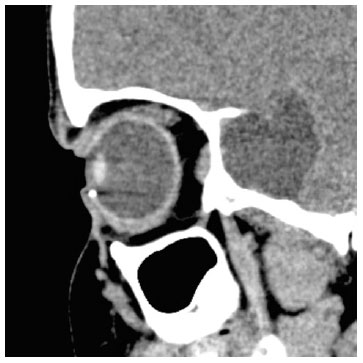

Radiography showed an image suggestive of IOFB, but details could not be assessed. Therefore, computed tomography of the orbits was performed, which provided evidence of a metallic and cylindric IOFB in the anterior chamber topography (Figures 3 and 4).

08-fig03.jpg)